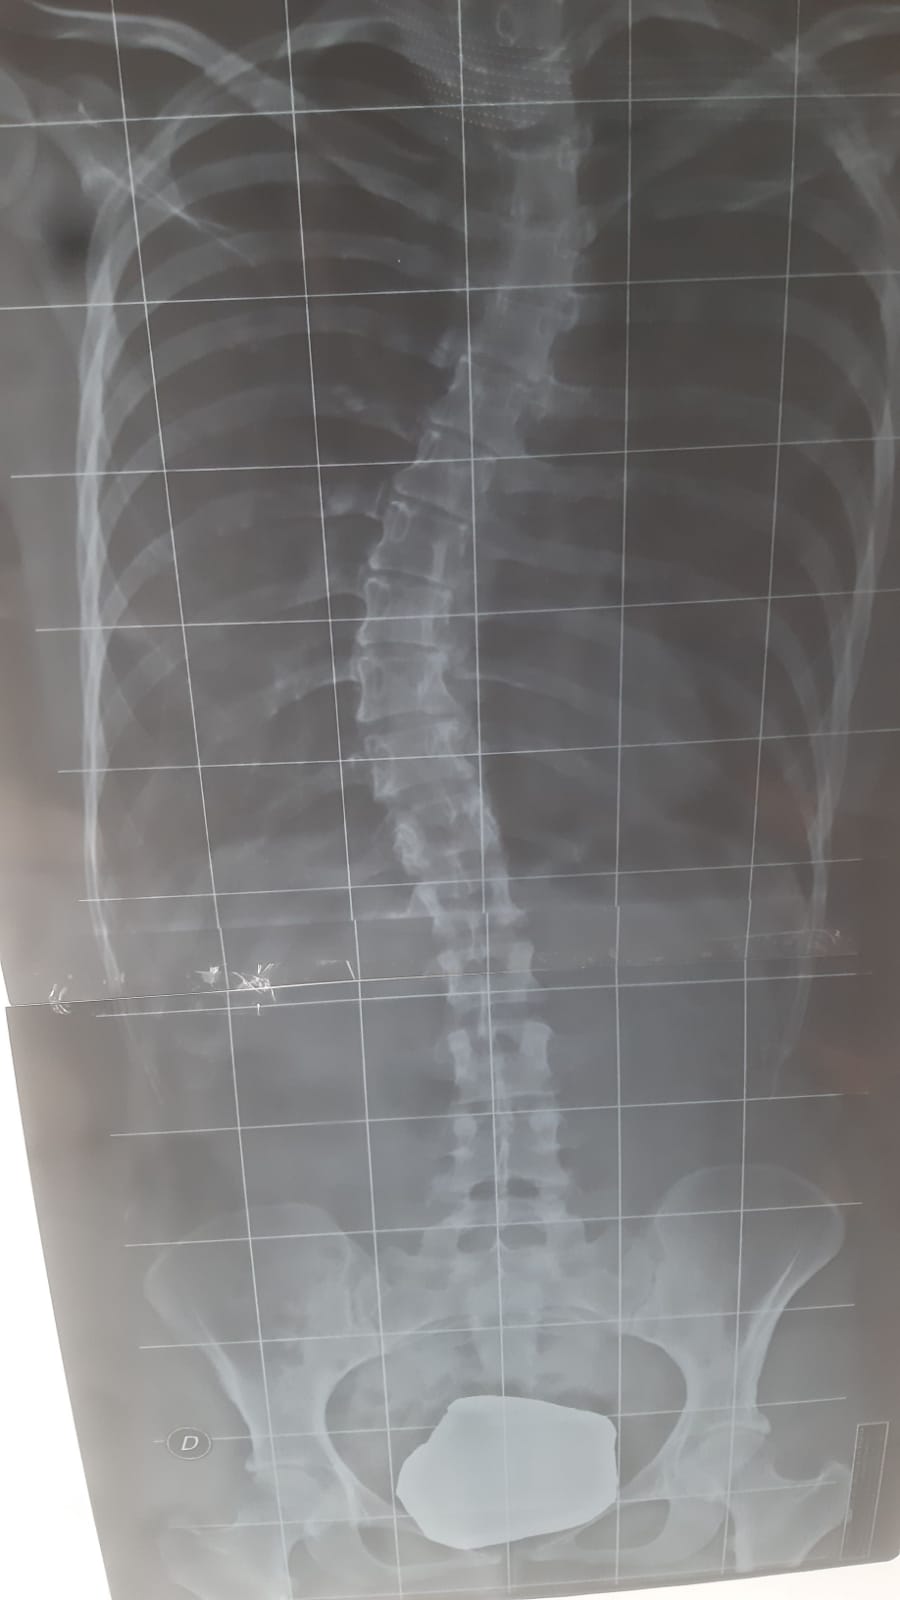

Salve volevo indicazioni su questa patologia in quanto tempo si potrebbe recupera qualche grado visto che devo fare ricorso per un concorso mi hanno detto che superi il 25% ma senza scriverlo sul referto se fosse vero con un

Busto quanto tempo ci vorrebbe per recuperare almeno al 20?? [vi allego il file datemi consigli visto che un anno fa non avevo niente ho 25 anni.